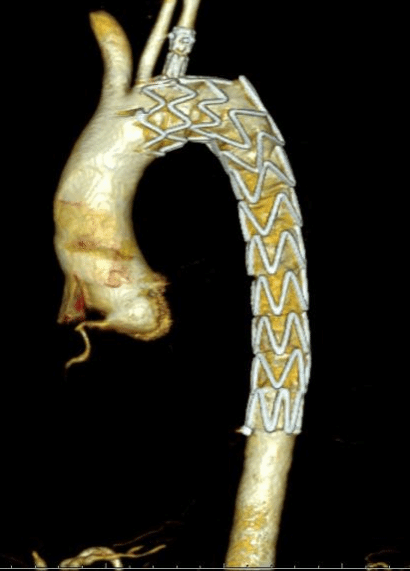

主动脉“修复”介入诊疗技术:

术后CT复查图: